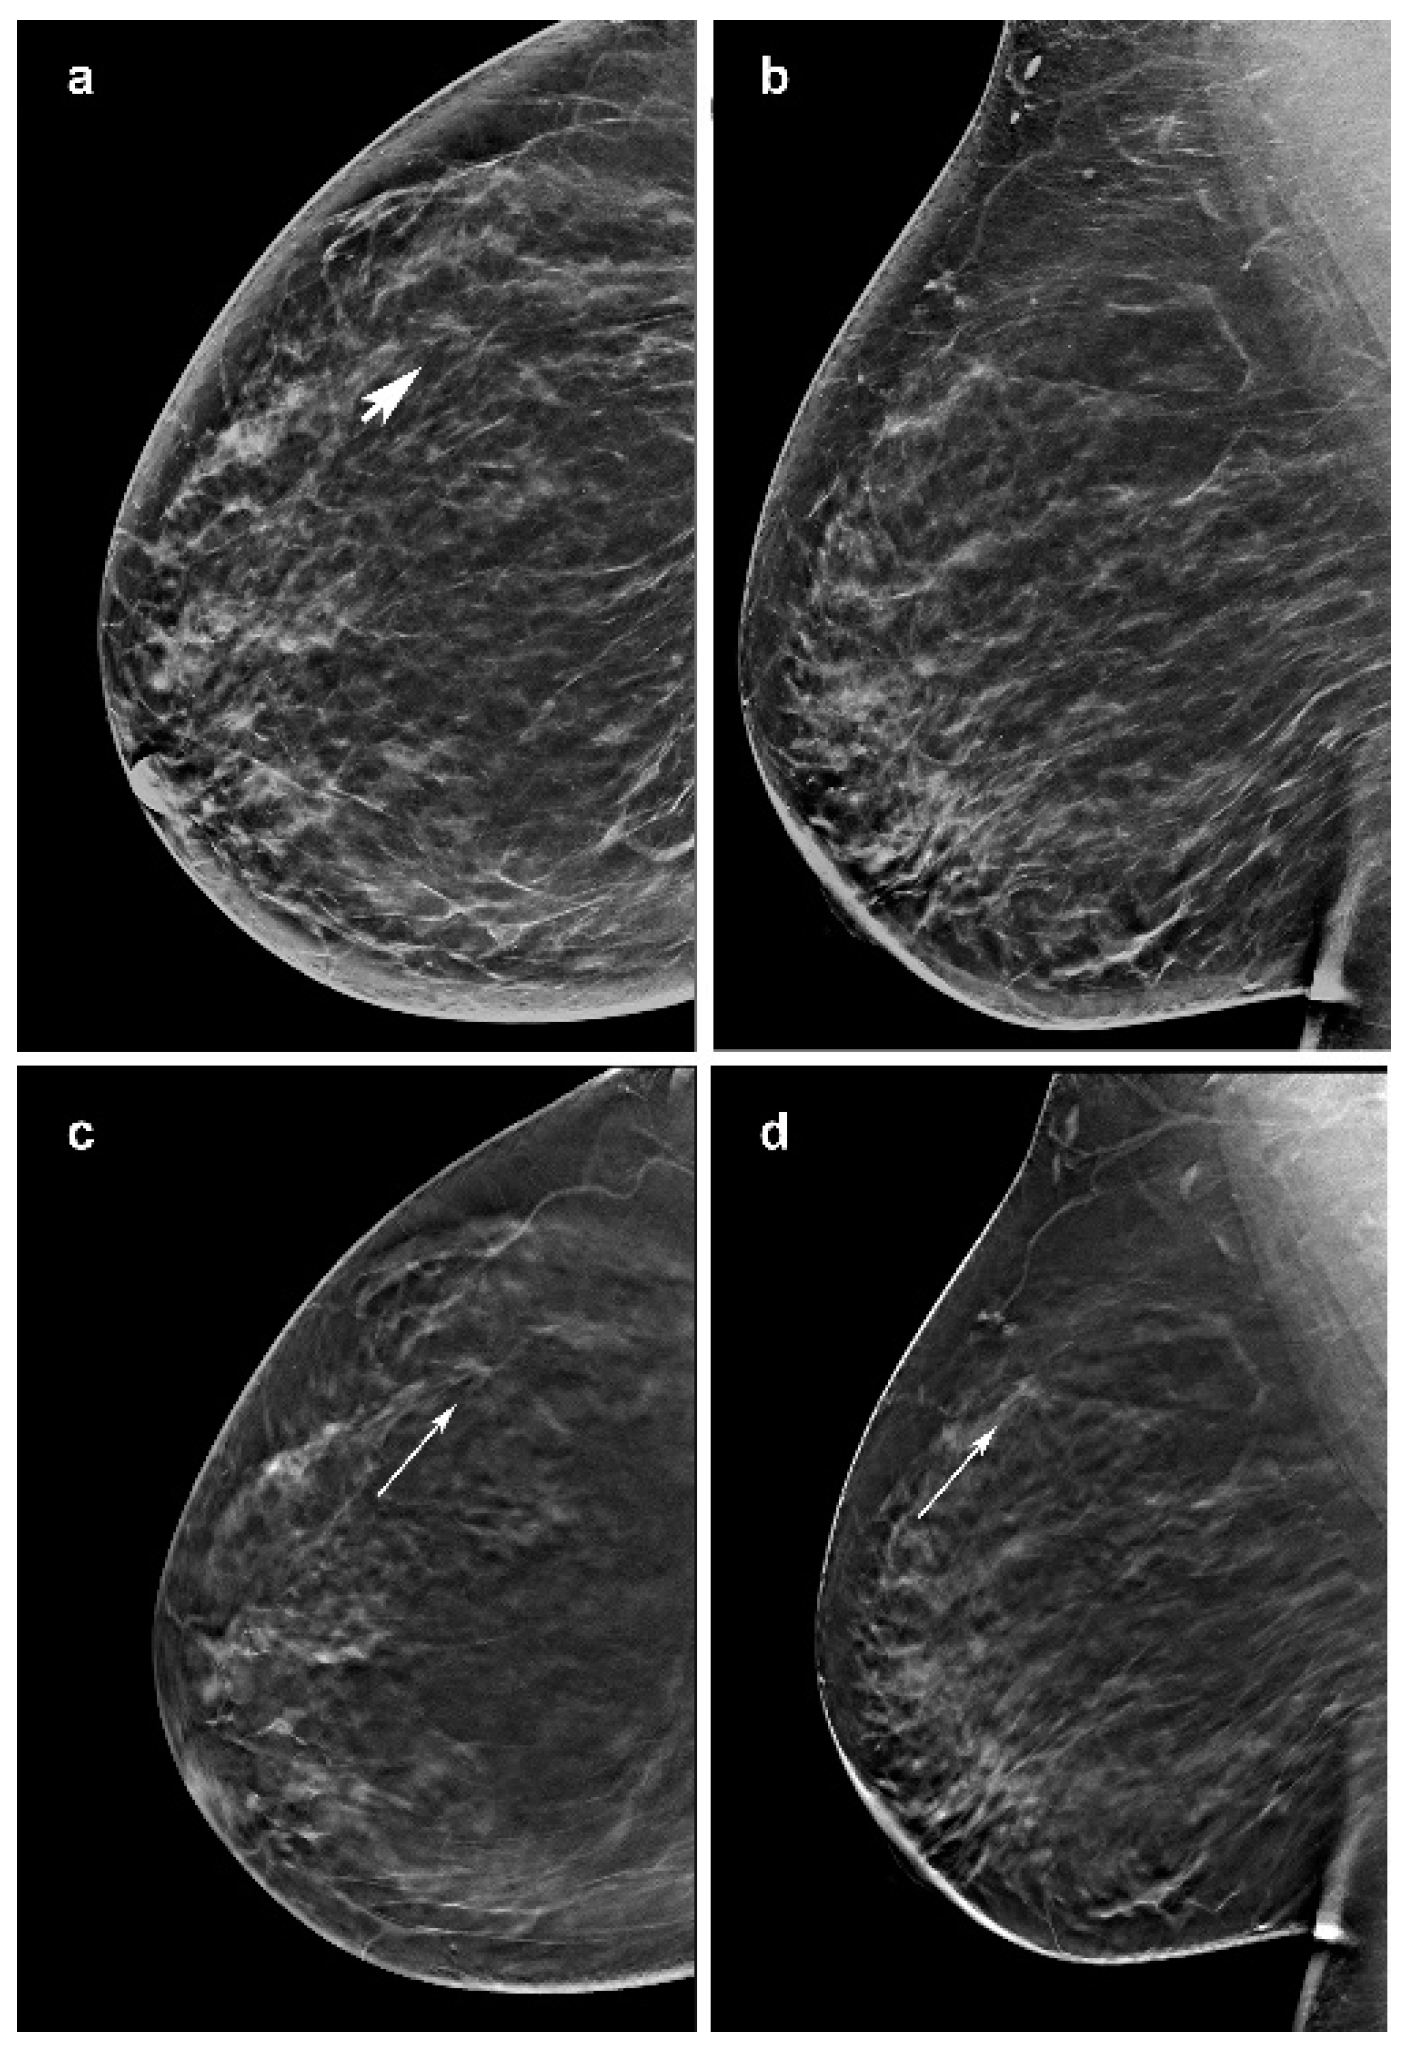

Figure 1.

Images of a 56-year-woman with an invasive lobular carcinoma diagnosed at screening digital breast tomosynt 20 mm in the outer inferior quadrant (arrow) (a–c). (d) It is further less defined in the mediolateral oblique images of the DBT (arrow).

Focusing on its histopathological architecture, ILCs usually extend in a single-file growth pattern, with little desmoplastic reaction and no hemorrhage or necrosis, that appear with specific features on imaging. Previous results supported that the use of DBT highlights architectural distortions defining lesion margins or spiculation [12]. When these contrast differences are small, mostly in dense breasts, our data confirm that the detection of ILC on mammography becomes increasingly difficult. In our series, 38% (8/21) of architectural distortions were difficult cases on imaging. All readers did not visualize four architectural distortions in dense breast on synt2D, although these lesions were visible on DBT. These architectural distortions are challenging for the breast radiologist, even regarding its diameter size, ranging between 15 to 30 mm, with a mean of 21 mm (Figure 1). While one architectural distortion of 12 mm in a dense breast was recognized in 3D DBT by only three readers, three architectural distortions in fatty breast were seen in DBT by all the readers but one. These data are in line with several studies [12] showing that DBT has better capabilities than synt2D in lesion detection and characterization; removing the tissue above and below the plane of the lesion means the size and margins can be more readily assessed.